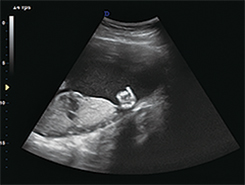

广泛应用于腹部、泌尿科、妇产科、儿科/新生儿科、浅表组织、肌肉骨骼、心脏等

声束扇形扩展技术:不用拼接保障高速高质

交叉发射和接收:消除侧边效应

全数字化超宽频带:提高分辨率和穿透率

支持多种探头:腹部、心脏、小器官、腔体探头、直肠探头、容积探头